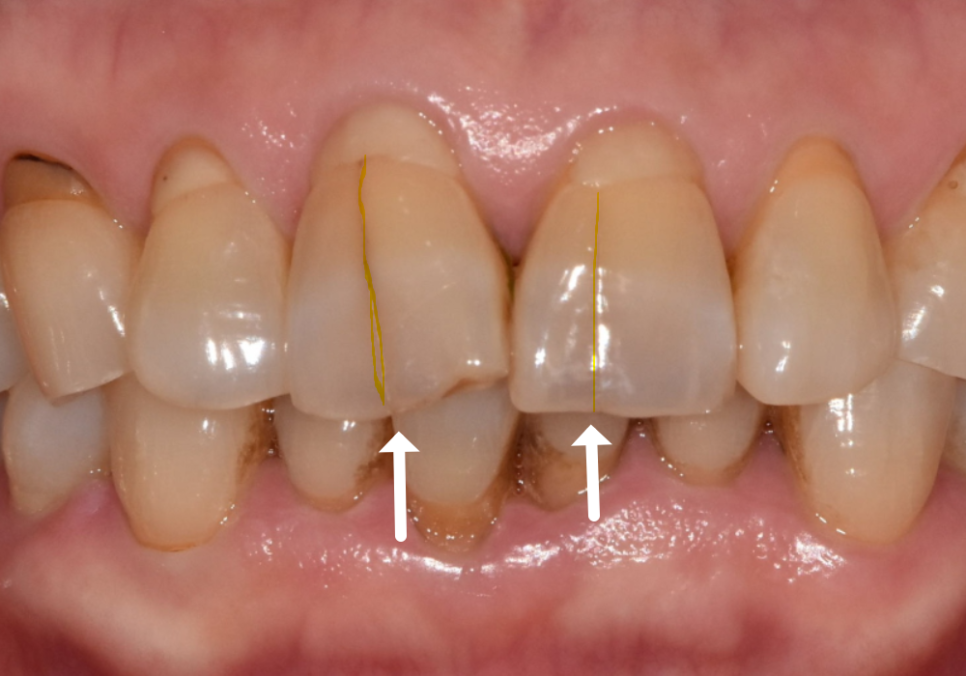

얼마 전 가운데 앞니(#11, 21)가 까맣게 변해서

걱정스러운 마음으로 내원하신 환자분이 계셨어요.

치아를 살펴보니

전체가 어둡게 변한 게 아니라,

마모된 끝부분 위주로

까맣게 변색된 모습이었습니다.

처음에는 치아 신경이 손상되어

'실활치 변색'은 아닐까 의심해 볼 수도 있는데요.

하지만 이 환자분은 과거에

신경치료를 받으신 적이 전혀 없으셨고,

변색 역시 치아 전체가 아닌

마모된 끝부분에만 한정되어 있었어요.

여러 정황을 종합해 볼 때,

신경 문제라기보다는

마모로 인해 약해진 틈 사이로

충치가 진행된 것으로 판단되었습니다.